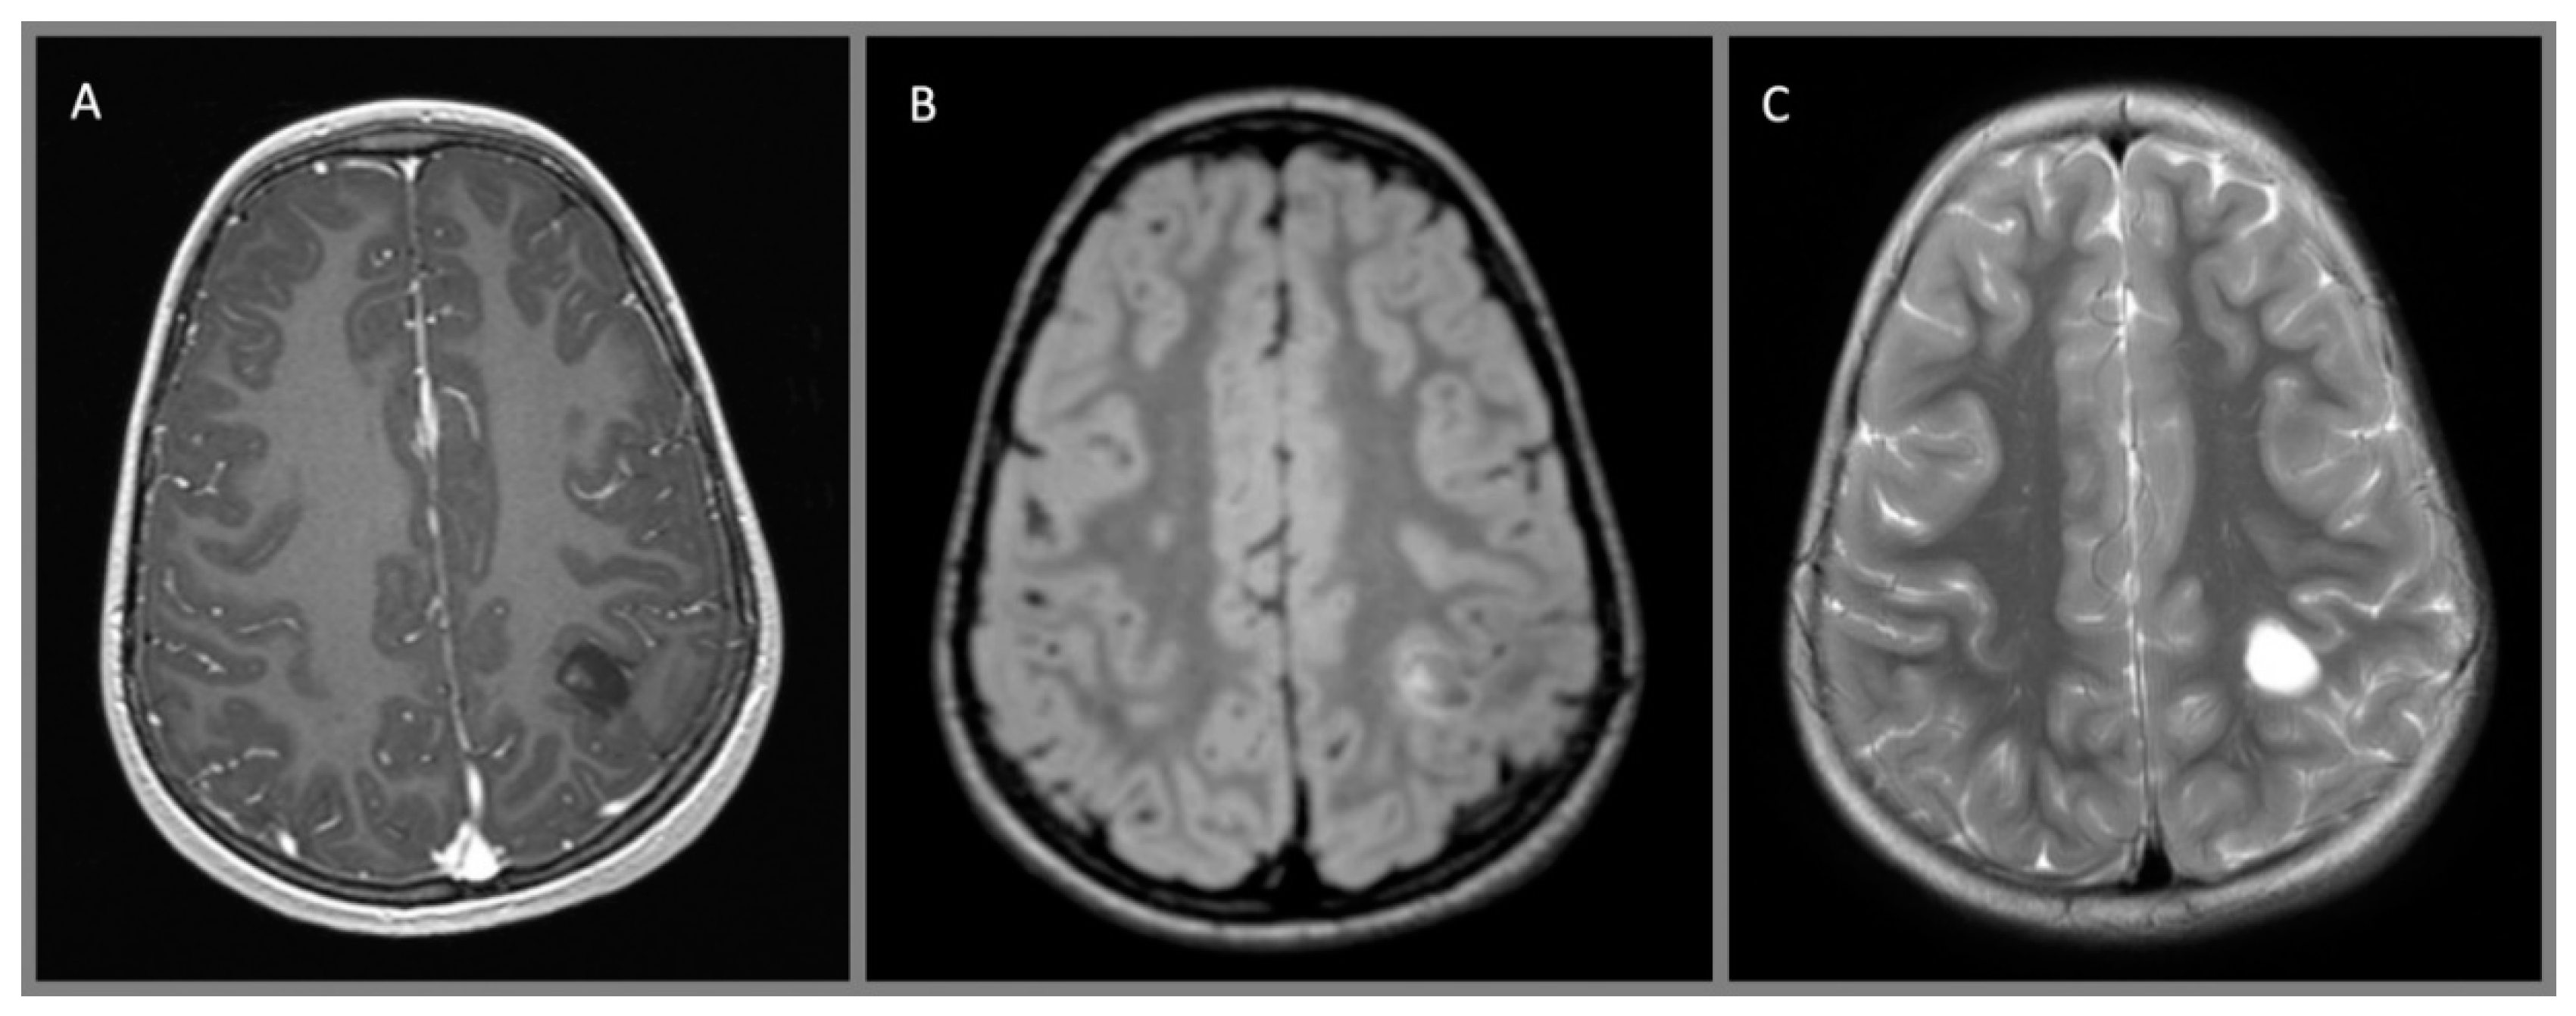

4. Diagnostic Studies

5.2. Surgical Planning